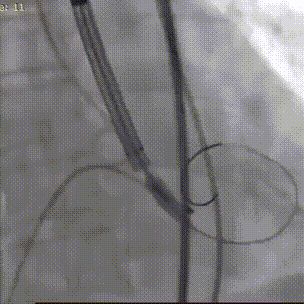

精准定位

逐步释放瓣膜

后扩